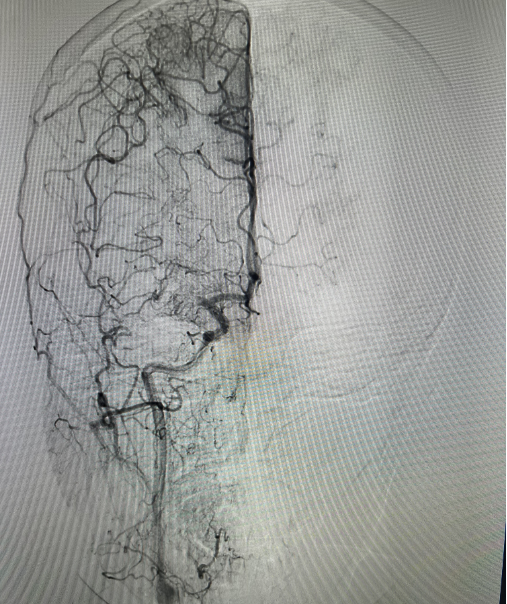

全脑血管造影